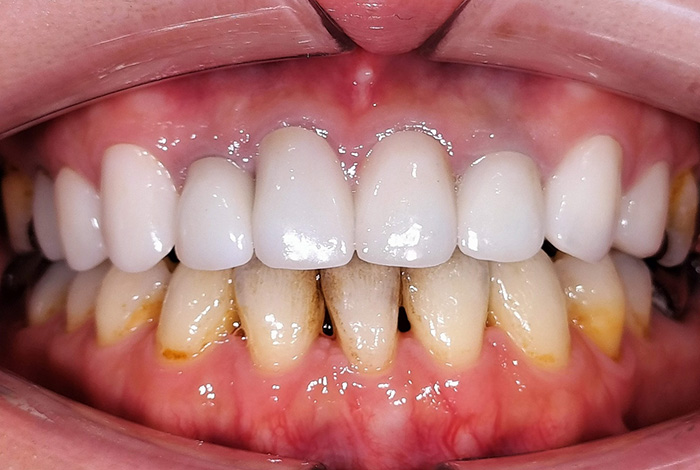

Before

After

前歯の見た目と噛み合わせのバランスを整えたケース

「前歯が強くかみ込んでいる気がする」「歯並びだけでなく、噛み合わせも気になる」

今回の患者様は、ディープバイト(過蓋咬合)による前歯の見た目と噛み合わせを気にされて来院されました。ディープバイトとは、上の前歯が下の前歯に深く重なっている噛み合わせのことで、見た目の問題だけでなく、前歯や顎への負担につながることがあります。

本症例では、マウスピース型矯正装置(インビザライン)を用いて治療を行いました。合計84枚のアライナーを使用し、歯並びだけでなく咬合の深さにも配慮しながら治療を進めました。

治療後は、前歯の見た目のバランスが整い、噛み合わせも改善しました。